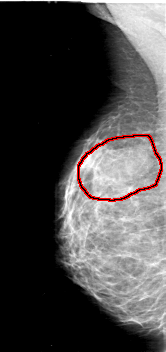

D_4037_1.RIGHT_CC

RIGHT_CC LINES 5281 PIXELS_PER_LINE 2476 BITS_PER_PIXEL 12 RESOLUTION 43.5 OVERLAY

FILE: D_4037_1.RIGHT_CC.OVERLAY

TOTAL_ABNORMALITIES 1

ABNORMALITY 1

LESION_TYPE MASS SHAPE OVAL MARGINS OBSCURED

ASSESSMENT 0

SUBTLETY 4

PATHOLOGY BENIGN

TOTAL_OUTLINES 1

BOUNDARY